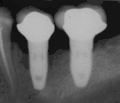

- с помощью рентгенографии изучаются качество и плотность костной ткани;